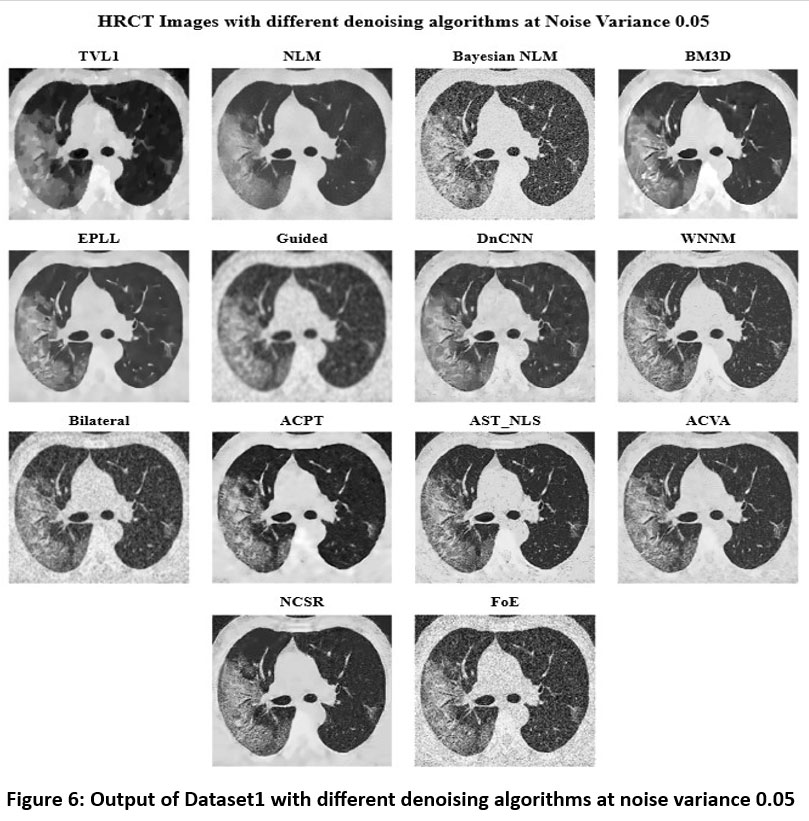

![]() |

Figure 6: Output of Dataset1 with different denoising algorithms at noise variance 0.05 |

Figure 6 shows the denoised HRCT images using a variety of algorithms at a Noise Variance (N.V.) of 0.05. Among the methods, BM3D remains one of the best-performing techniques, effectively suppressing noise while maintaining fine anatomical structures with clear contrast. DnCNN also demonstrates strong performance, preserving sharp edges and lung structures while reducing noise, making it a reliable deep-learning-based denoising approach. WNNM continues to have the denoising capability without significant noise reduction but the loss in the fine details. Guided Filtering and EPLL significantly remove the noise, but the amount of over-smoothing diminishes the visibility of the small lung structures. Bilateral Filtering gives medium denoising performance but continues to exhibit a lot of noise artifacts with the blurring of fine details. ACPT, AST_NLS, and ACVA balance noise removal with structural preservation, with ACVA producing relatively clearer results. However, Bayesian NLM and NLM (Non-Local Means) suffer at the cost of noise variance with increased graininess, but a lesser sharpness level. Noisiness is more prevalent with FoE and NCSR than with other techniques since they cannot successfully remove the noise while retaining structural integrity. The worst one was TVL1 (Total Variation L1 Norm), highly over-smoothing and anatomically distorted. As the noise variance increases to 0.05, BM3D and DnCNN continue to demonstrate the best balance between noise suppression and structural preservation, making them the most effective choices for medical imaging. WNNM and ACVA offer moderate results but still introduce some loss of fine details. In contrast, TVL1, FoE, and Bayesian NLM struggle to produce clinically viable outputs due to excessive blurring or retained noise artifacts. At higher values of noise, deep learning types such as DnCNN and advanced filtering types like BM3D are more preferred in medical imaging, where anatomical structures have to be preserved for precise diagnosis.